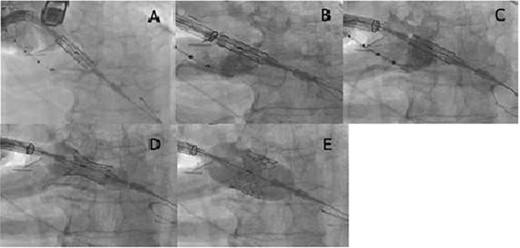

(A) The Sapien S3 did not pass into the aortic valve, and the Certitude system bounced back toward reverse direction; (B) the Sapien S3 was forcefully pushed together with the Certitude system, and the Sapien S3 finally came into the aortic valve; (C) the Certitude system was pulled back to enable dilatation; (D) the Sapien S3 was slowly deployed to avoid malposition; (E) the Sapien S3 was completely deployed

We then decided on a third option of pushing the Sapien S3 forcefully together with the Certitude system (Fig. 1B). With careful pulling, enough countertraction was given to the Safari wire to ensure the direct transmission of power to the Sapien S3 while simultaneously avoiding injury to the left ventricle by the Safari wire. The Sapien S3 was successfully brought into the aortic valve. Thereafter, the Certitude system was pulled back to near the aortic wall (Fig. 1C), and the Sapien S3 could be deployed as usual (Fig. 1D and E). The postoperative course was uneventful and the patient was discharged home on the 10th postoperative day.